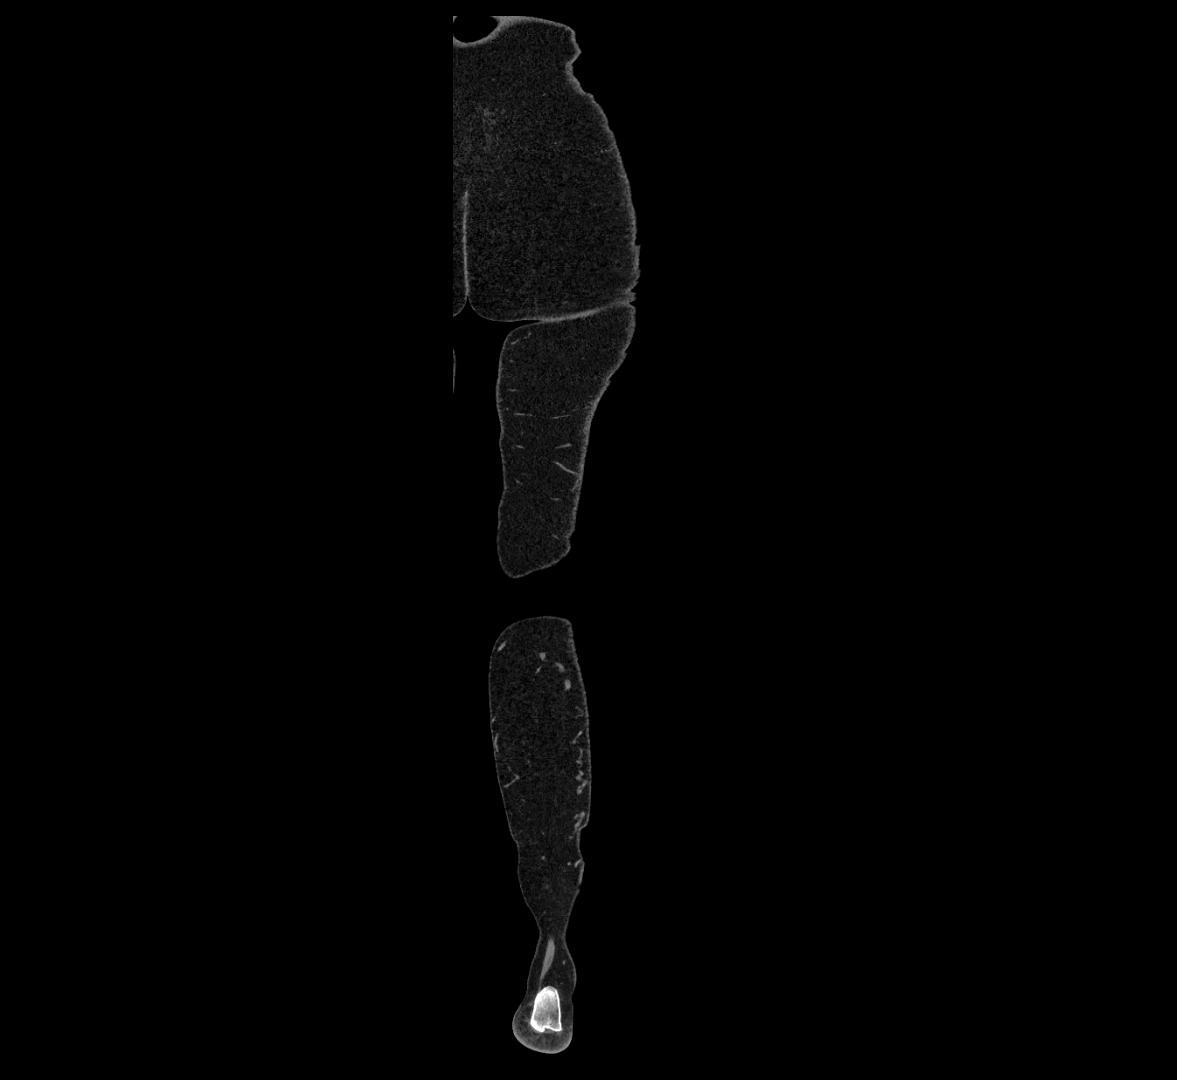

MRI images

image